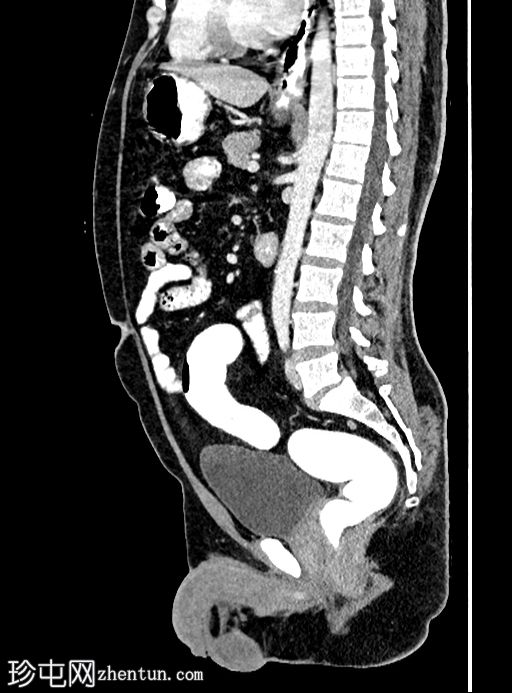

矢状位增强扫描

门静脉期

乙状结肠旁可见两处小的脂肪衰减病灶。较小的病灶呈周边环状强化,伴有轻度邻近脂肪条索状改变 → 急性大网膜垂炎。

较大的病灶呈薄环状强化,周围无炎症 → 消退期/慢

性病

变。未见肠壁增厚,未见肠腔相通,无游离液体或积液。